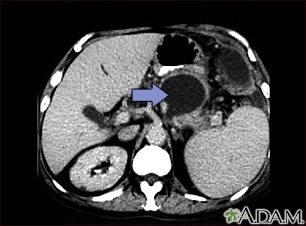

An abdominal CT scan is an imaging test that uses x-rays to create cross-sectional pictures of the belly area. CT stands for computed tomography.

The abdominal CT scan may show some cancers, including:

- Renal cell carcinoma (kidney cancer)

The abdominal CT scan may reveal the following kidney problems: